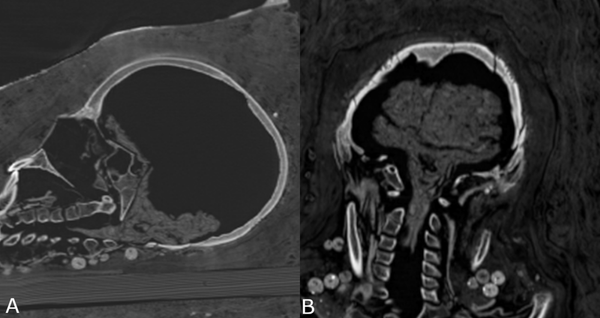

Agora, tomografia computorizada revelou que ao menos uma das três múmias foi enterrada com os órgãos (até o cérebro) e que as duas mulheres foram enterradas com belos colares, encontrados pelos pesquisadores.

A análise da tomografia computadorizada revelou vários problemas de saúde, inclusive artrite sofrida pela mulher.

As múmias, depois de passarem por vários donos, acabaram nas Coleções de Arte de Dresden, na Alemanha, onde foram submetidas a raios-X no fim dos anos 80. No entanto, tomografia computadorizada revelou muito mais sobre o interior das múmias.